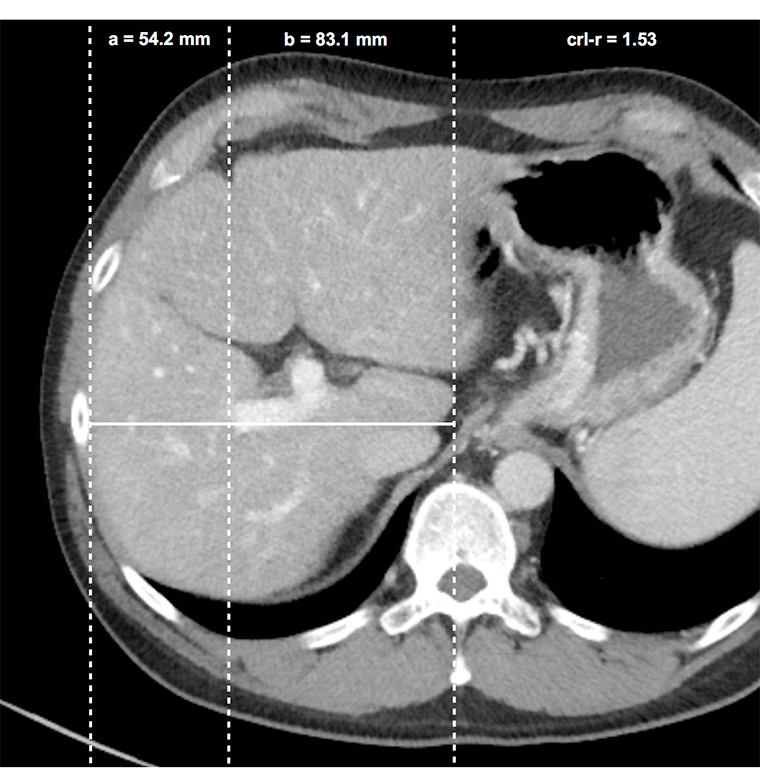

Figure 3

Caudate right-lobe ratio (crl-r) in a patient with liver fibrosis. In axial planes distances of the right lateral border of the right portal vein bifurcation to the lateral margin of the right hepatic lobe (a) and to the most medial margin of the caudate lobe (b) are measured in an exactly horizontal direction. The two distances were divided b / a (caudate lobe / right lobe) and defined as the caudate-right-lobe ratio (crl-r).

Images of all 148 patients (80 cirrhosis, 35 precirrhotic fibrosis and 33 control patients) were acquired by a 64–row-CT-unit Somatom Sensation 64 (24 x 1.2 mm, pitch 0.8, slice 1.5/5 mm, Siemens, Erlangen, Germany). Exclusively, 5-mm axial CT slices of portal-venous abdominal CT-scans were used. The scans were systematically reviewed in consensus by two radiologists with 2 and 10 years of experience in abdominal imaging, who were blinded to any clinical and imaging results or histological fibrosis stage. The diameters of the three main liver veins were measured 1–2 cm before their aperture into the inferior caval vein (fig. 2) and added to give a sum (ld-score). Accessory hepatic vein branches were not measured. The caudate-right lobe ratio (crl-r) was calculated as described by Awaya et al. [18]. Distance from the right lateral border of the first bifurcation of the right portal vein to the medial border of the caudate lobe and to the lateral border of the right liver lobe were divided as illustrated in figure 3.